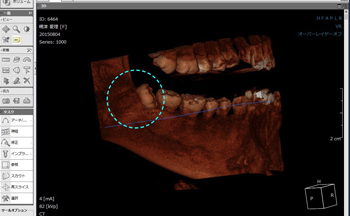

手術時間は「1時間以内」が条件(午後診が始まるまでの間)となるためCT画像で親知らずを縦分割、横分割にして歯の形状を分析して、最短時間での抜歯の準備を行う。

上記の3D画像からも分かるように内側(舌側)への傾斜もきつかったため、歯を分割する際、「舌を傷つけない」事に最も気を配りました。